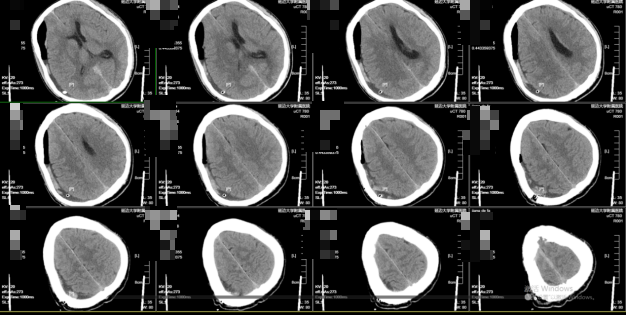

56岁男性患者,既往因患肝癌行手术治疗及脾脏切除术等。该患者因“突发意识不清、右侧瞳孔散大约1小时”为主诉于急诊入院。头部CT示右额颞顶枕部慢性硬膜下血肿,右侧侧脑室受压,伴中线结构左移>1.5cm,脑疝形成!左侧额部慢性硬膜下血肿。血栓弹力图:R(凝血因子活性)3.4min(偏低,5-10min为正常值),提示凝血功能异常,可能增加出血风险。

图1入院头部CT